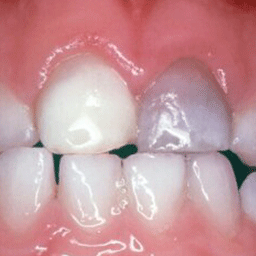

앞니 크라운

Before

After

외상으로 파절된 앞니를 자연스럽게 복원